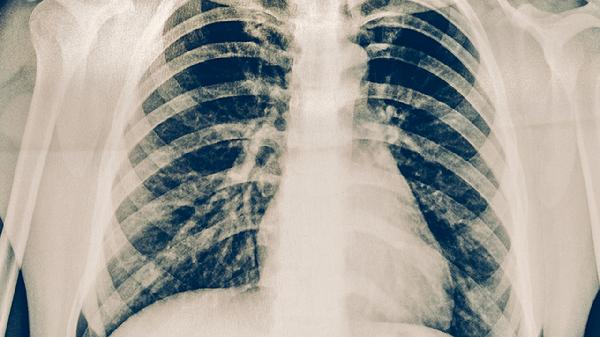

肺癌引起的發(fā)燒通常表現(xiàn)為持續(xù)性低熱,也可能出現(xiàn)不規(guī)則高熱,常伴有咳嗽加劇、體重下降等腫瘤相關(guān)癥狀。

肺癌患者的發(fā)熱多呈現(xiàn)間歇性低熱狀態(tài),體溫通常在37.5-38.5攝氏度之間波動。這種發(fā)熱與腫瘤細(xì)胞釋放的致熱原有關(guān),當(dāng)腫瘤組織發(fā)生壞死或繼發(fā)感染時,體溫可能出現(xiàn)階段性升高。不同于普通感染性發(fā)熱,這種發(fā)熱對抗生素治療反應(yīng)不佳,且隨著腫瘤進(jìn)展發(fā)熱持續(xù)時間可能延長。

肺癌發(fā)熱通常不具備典型熱型規(guī)律,既非稽留熱也非弛張熱。發(fā)熱周期與腫瘤生長周期可能存在關(guān)聯(lián),當(dāng)腫瘤侵犯支氣管導(dǎo)致阻塞性肺炎時,可突發(fā)高熱伴寒戰(zhàn)。腫瘤熱使用非甾體抗炎藥通常有效,但停藥后容易反復(fù)發(fā)作。

肺癌發(fā)熱需與藥物熱、機會性感染及副腫瘤綜合征相區(qū)分。腫瘤熱多在午后出現(xiàn),很少超過39攝氏度,且患者自覺癥狀與體溫不成正比。當(dāng)出現(xiàn)高熱伴膿毒血癥表現(xiàn)時,提示可能并發(fā)阻塞性肺炎或肺膿腫。